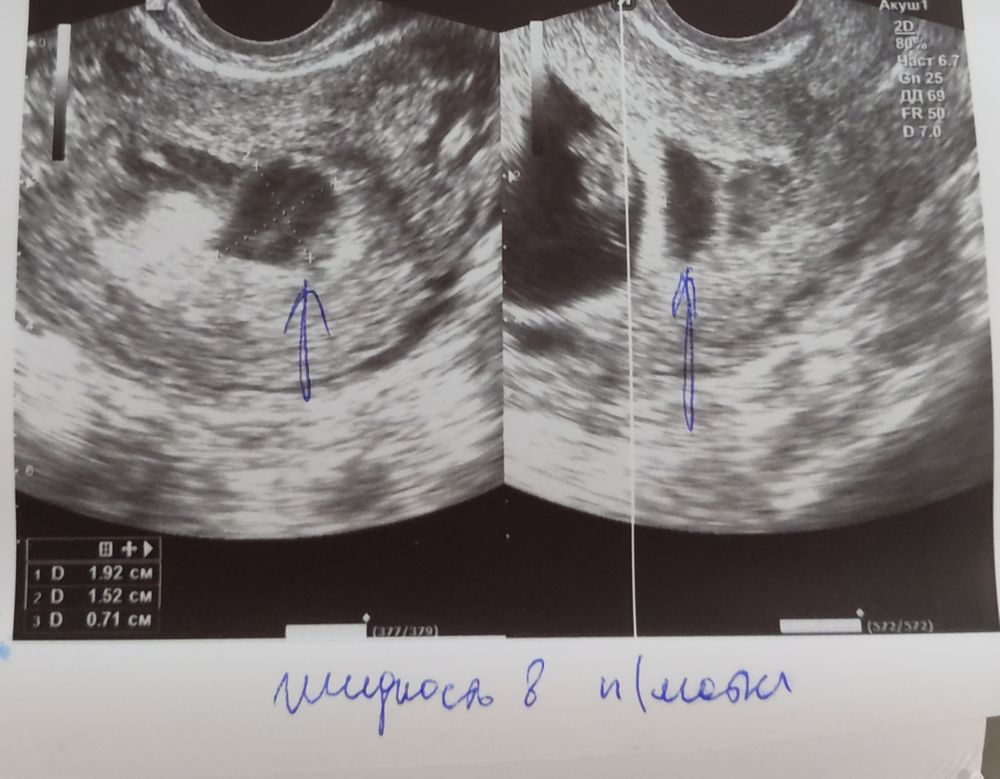

У меня жидкость внизу плодного яйца, гематому не написали.

Откуда может быть эта жидкость?

Жанна, но гениколог не стала писать гематома, а жидкость в полости матки в нижнем сегменте около 1 мл